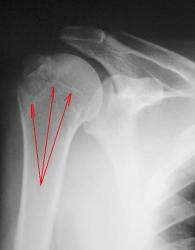

"Перелом-отрыв бугорка плечевой кости", так любят его наши травматологи, так и называют.

Соглашусь с коллегой Ореховым! Оторвался бугорок!

Ну, и по всей видимости, перелом, без смещения костных отломков.